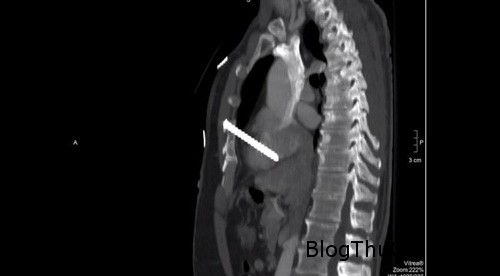

Kết quả chụp X-quang cho thấy chiếc đinh găm đúng vào tim ông Rakow, chỉ cách động mạch vành có 2mm. Ảnh: Youtube

Tai nạn xảy ra khi ông Eugene Rakow, 58 tuổi, sống ở bang Minnesota, đang đóng sàn nhà cho người hàng xóm hôm 27/9. Chiếc đinh dài 3,5 inch (khoảng 7,6 cm) không may găm đúng vào ngực ông, cách động mạch vành chỉ 2mm.

Các bác sĩ tiến hành phẫu thuật tim cho ông Rakow nói rằng ông là người may mắn nhất thế giới khi vẫn còn sống sót sau tai nạn nguy hiểm trên. “Bác sĩ nói 9 trong 10 người sẽ không thể qua khỏi nếu họ rơi vào tình huống như tôi”, ông Rakow kể lại.